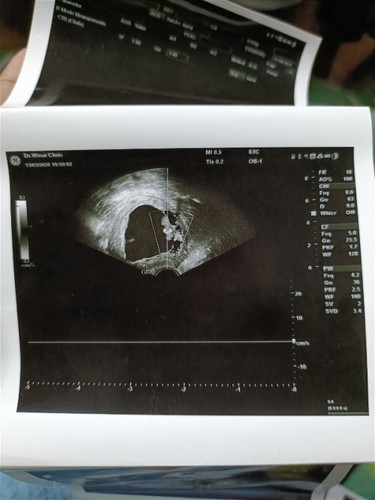

สอบถามหน่อยค่ะ มีเลือดออก และไปหาหมอ หมอซาวด์ดูบอกว่าไม่เห็นหัวใจน้องเต้น หมอบอกว่าเด็กหยุดการเติบโตตั้งแต่8วีค ตอนนี้12วีคแล้ว ก่อนหน้านี้ไม่มีอาการไรเลย เพราะไปฝากท้องตอน8วีค 3วัน แม่ๆๆบ้านไหนเป็นแบบนี้บ้าง ยังพอมีปาฏิหาริย์มั้ยค่ะ เพราะท้องแรกก็เด็กหยุดการเติบโต คนนี้ท้อง2ก็เป็นอีก กังวนมากๆๆ อยากมีลูกสักคน